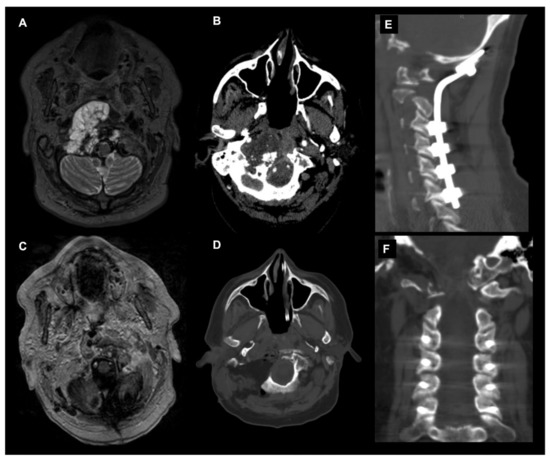

The posterior and posterolateral approaches represent two further operative techniques for the treatment of CVJ primary and metastatic neoplastic diseases available in the neurosurgical armamentarium (Figure 6).

Figure 6.

Combined endoscopic endonasal approach and far-lateral transcondylar and petro-occipital trans-sigmoid approach to recurrent CVJ chordoma and subsequent occipitocervical fixation. Axial T2-weighted MR image (A) and angio CT scan (B) showing a recurrent predominantly right craniovertebral junction chordoma. The chordoma infiltrates the rhinopharynx, C0-C1-C2 joint complex and the entire right occipital condyle. A combined endoscopic endonasal approach associated with far-lateral transcondylar and petro-occipital trans-sigmoid approach has been performed. (C) Axial postoperative T1-weighted after contrast injection image and (D) noncontrast CT scan disclosed a gross total resection with the destruction of the right clival–atlo–axial joint. An occipital-cervical fixation was therefore postoperatively planned and performed (E,F).

The main variables determining the selection of the surgical approach are related to the tumor pathology, i.e., primary vs metastatic disease; anatomy, i.e., tumor location and involvement of the adjacent structures; and biomechanical considerations.